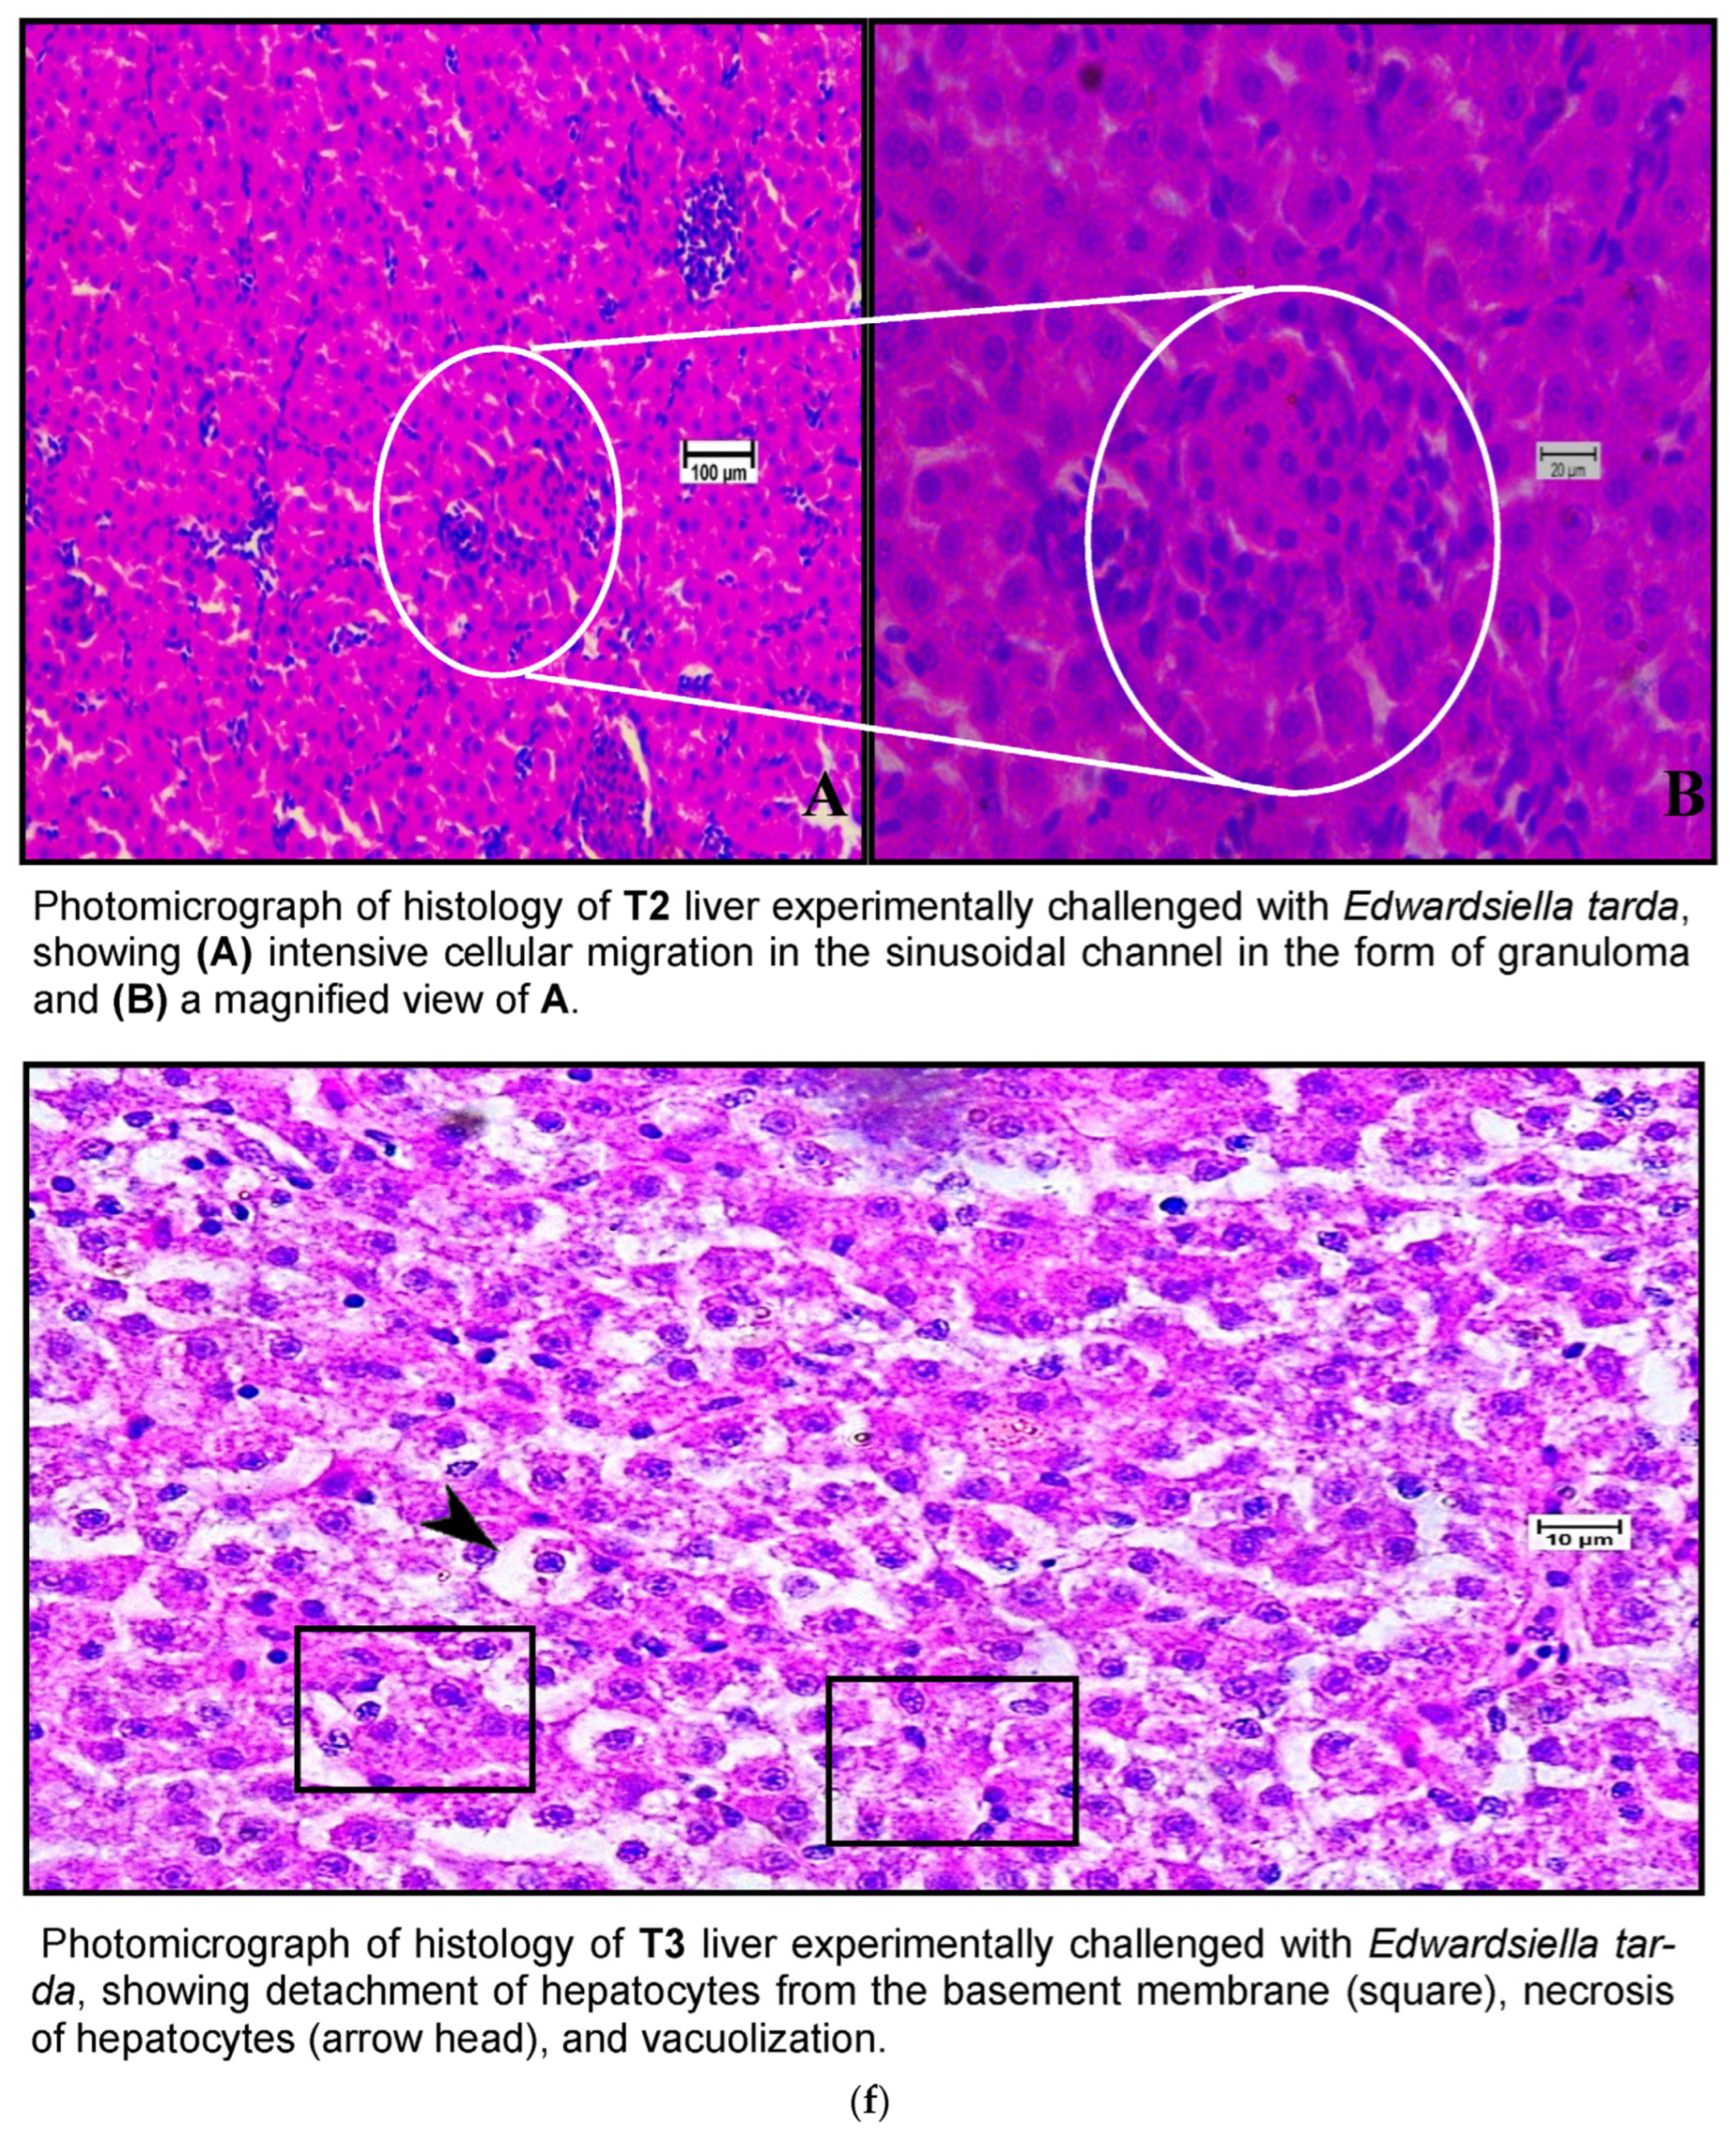

Histological examination of the livers of fish fed the control diet (CT) and the high-dose TABP diet (T3) revealed significant differences in the liver pathology (Figure 7a,b). The livers of fish fed the CT diet had a normal organization of polygonal hepatocytes, normal bile duct, and central vein. In contrast, the livers of fish fed the T3 diet showed fibrosis with fat deposits and altered the normal architecture of the hepatocytes. These findings are consistent with previous studies that have shown that high doses of TABP can cause liver damage in fish. The liver is a vital organ for fish, as it plays a role in digestion, absorption, metabolism, and detoxification. Liver damage can lead to a number of problems, including impaired growth, decreased reproduction, and increased susceptibility to disease. The findings of this study suggest that high doses of TABP can cause liver damage in fish, and further research is needed to determine the safe level of exposure for fish. In addition to the histological changes, the fish fed the T3 diet also had increased levels of oxidative stress markers in the liver. Oxidative stress is a condition that occurs when there is an imbalance between the production of free radicals and the body’s ability to remove them. Free radicals are unstable molecules that can damage cells and tissues. The increased levels of oxidative stress markers in the fish fed the T3 diet suggest that TABP may be causing oxidative stress in the liver, which could contribute to the liver damage observed in this study. The findings of this study provide evidence that high doses of TABP can cause liver damage in fish. Further research is needed to determine the safe level of exposure for fish and to identify the mechanisms by which TABP causes liver damage.

Figure 7.

(a) A photomicrograph of the livers of CT and T1 groups. (b) A photomicrograh of the livers of T2 and T3. (c) A photomicrograph of the livers of CT and T1 groups challenged with A. hydrophila. (d) A photomicrograph of the livers of T2 and T3 groups challenged with A. hydrophila. (e) A photomicrograph of the livers of CT and T1 infected with E. tarda. (f) A photomicrograph of the histology of the liver of T2 and T3 infected with E. tarda.